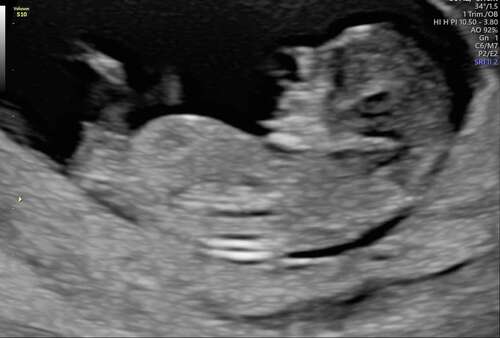

willen jullie met me mee kijken wat denken jullie dat het word ? 💙🩷❤️

Hoeveel weken? 12+ zeg ik meisje 🥰

11 weken 3dagen heb 2 foto's geplaatst vind je de andere ook een meisje?

Ja maar met deze termijn is dat heel normaal en kan het dus nog omhoog gaan en een alsnog een jongen blijken…